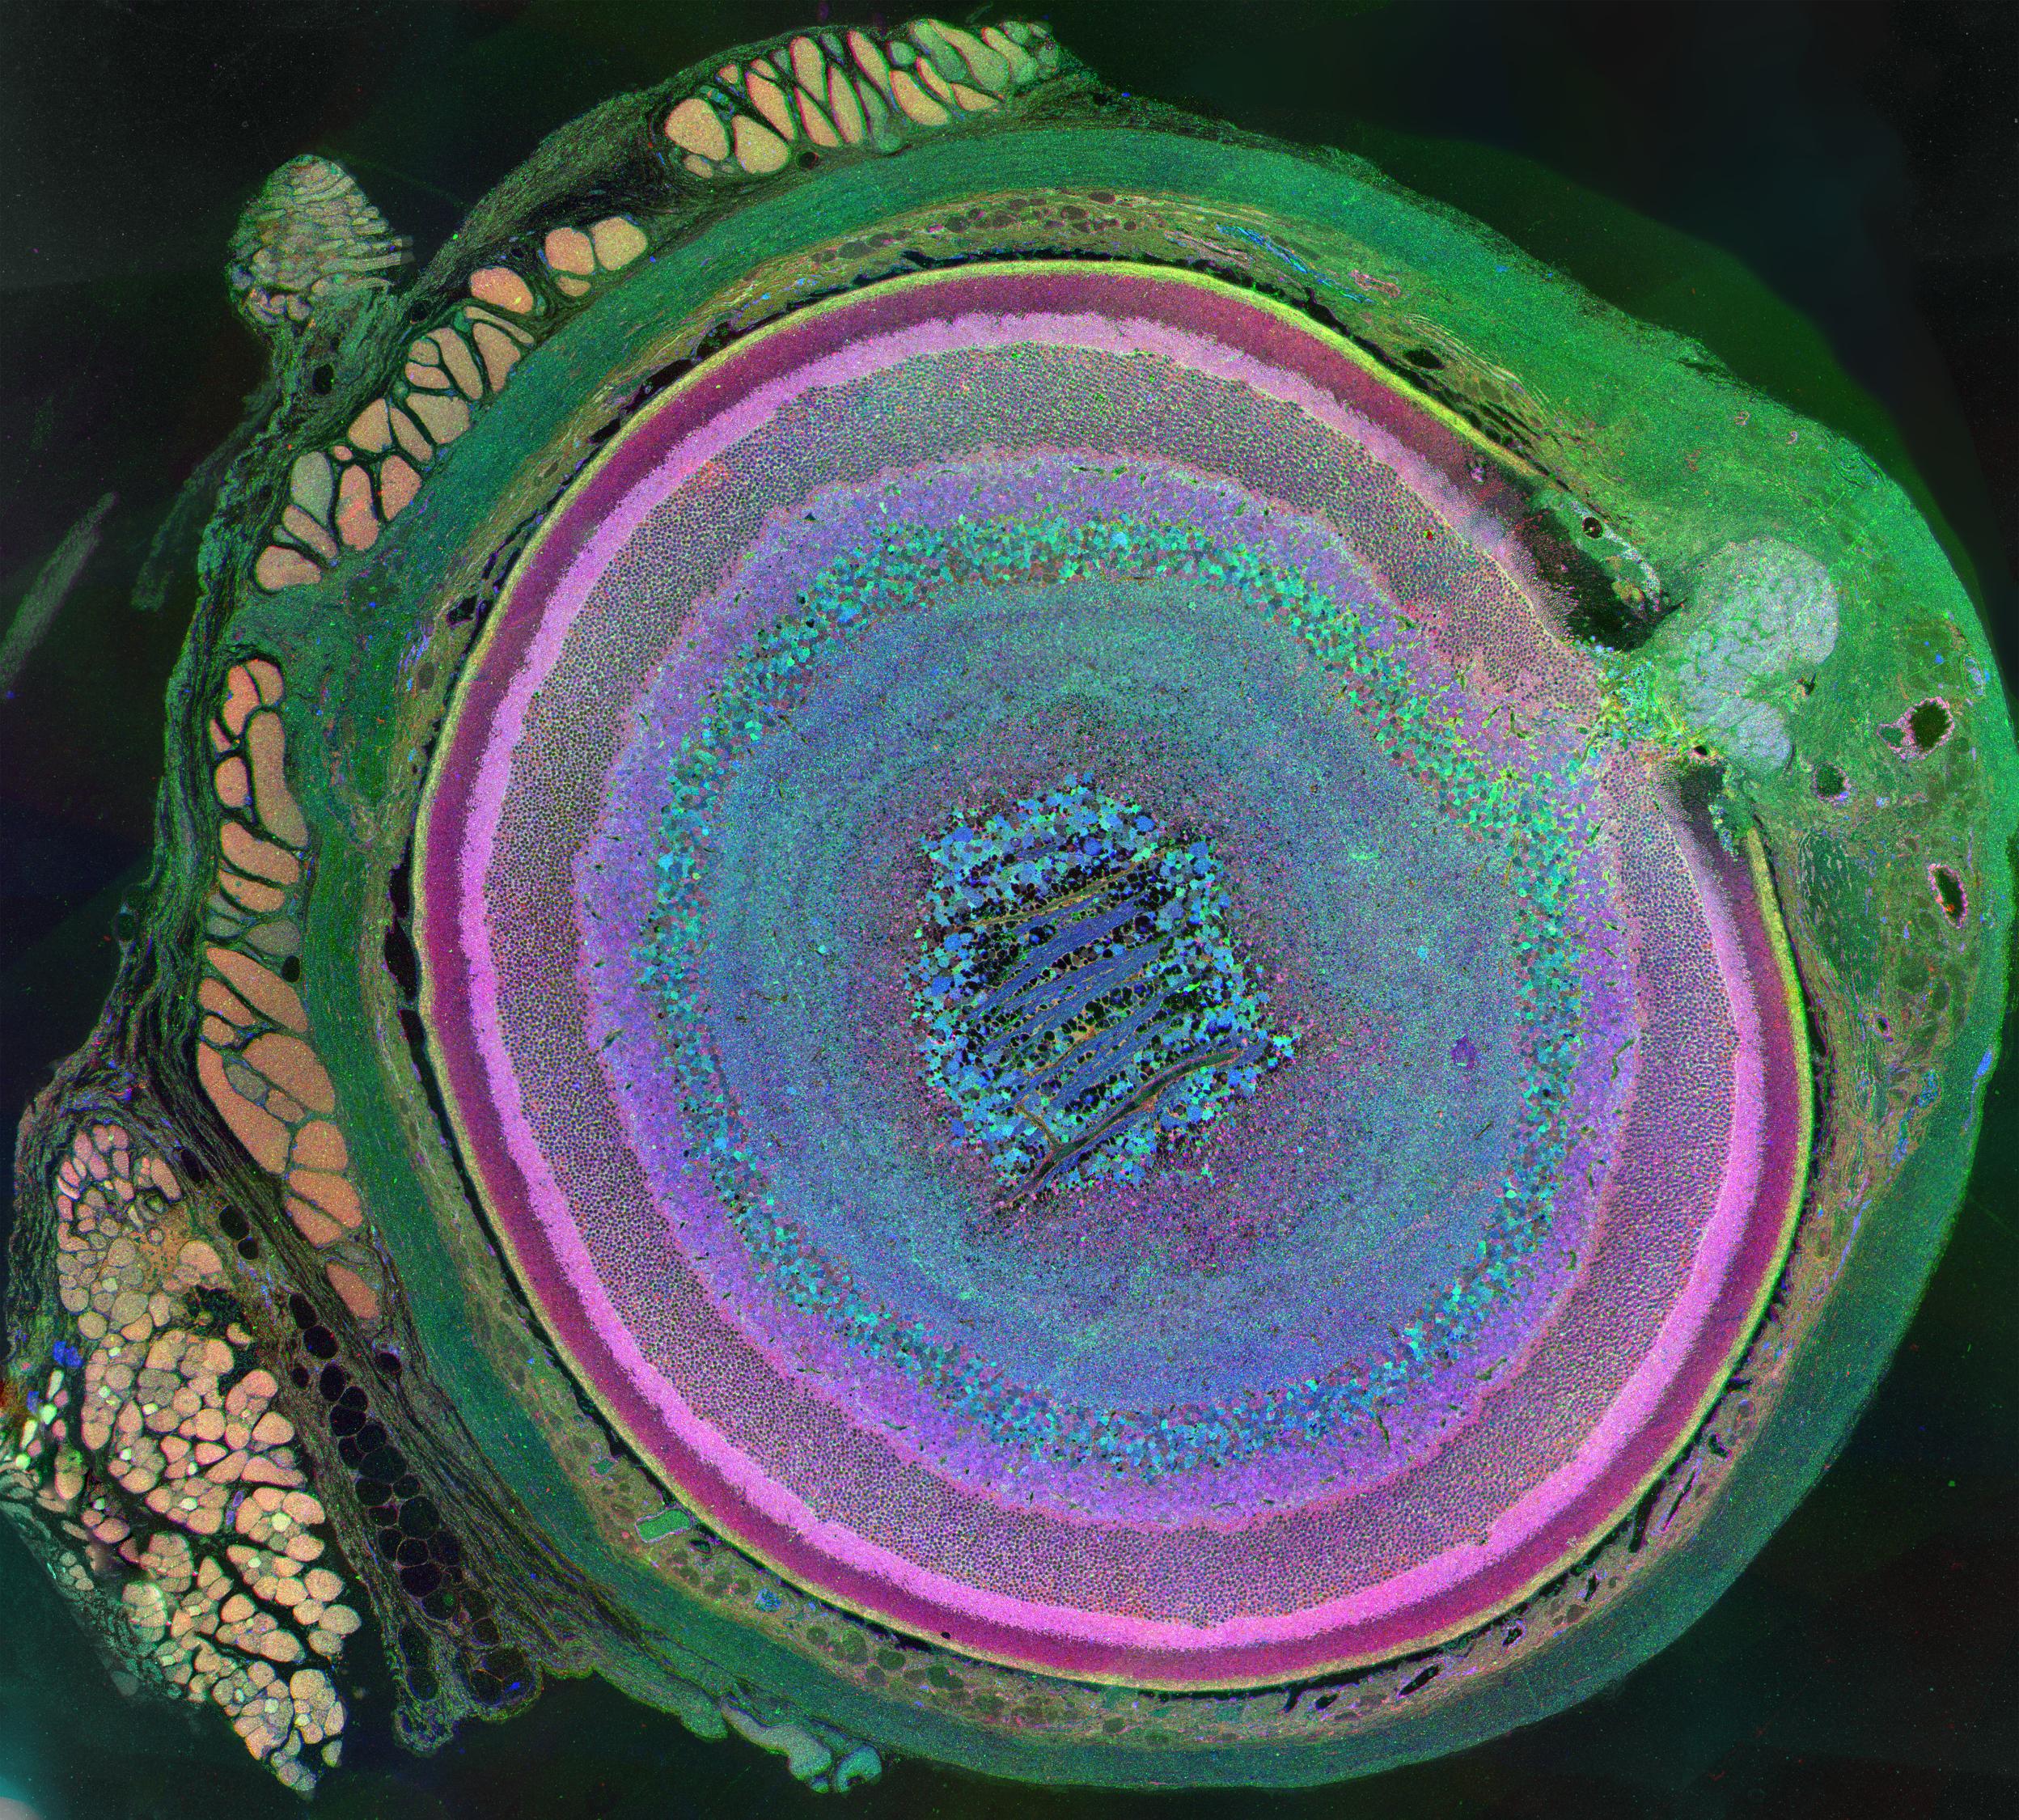

Age-related macular degeneration (AMD) is a common eye problem in older adults. It’s caused by inflammation that damages the macula, the part of the eye that controls sharp, straight-ahead vision. AMD is currently the most common cause of vision loss in adults over the age of 50 worldwide.

In studies in cells, fluoxetine blocked the inflammatory cascade set off by NLRP3 that eventually leads to damage in the eye. In a mouse model of dry AMD, injections of fluoxetine into the eye protected the macula from inflammation and degeneration. In contrast, eight other antidepressants didn't block AMD progression.